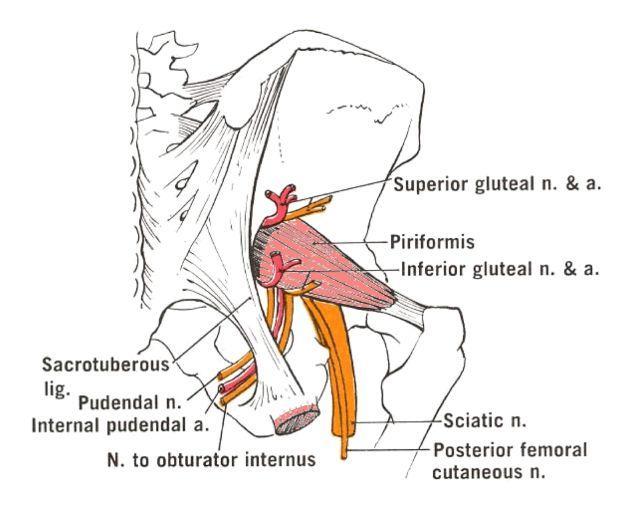

From which vertabrae does the superior gluteal nerve originate?

L4-S1

What is the pathway of the superior gluteal nerve?

exits pelvis through greater sciatic foramen. in the gluteal region it is located superior to the piriformis muscle and runs between gluteus medius and gluteus minimus

Which muscles does the superior gluteal nerve innervate?

gluteus medius, gluteus minimus, and the tensor fasciae latae muscle

From which spinal cord levels does the inferior gluteal nerve form?

L5.S2

What is the pathway of the inferior gluteal nerve through the body?

exits the pelvis through the greater sciatic foramen, is located inferior to the piriformis muscle in the gluteal region. runs just deep to gluteus maximus

What does the inferior gluteal nerve innervate?

gluteus maximus only

The sciatic nerve is formed from ventral rami from spinal cord levels ________-

L4 - S3

What is the path of the sciatic nerve?

exits the pelvis through the greater sciatic foramen. IN the posterior gluteal region, located inferior to piriformis m

origin course and distribution of superior gluteal nerve

O sacral plexus L4-S1

C leaves pelvis through greater sciatic foramen superior to piriformis; runs between gluteus medius and minimus

D gluteus medius, minimis, and TFL

origin course and distirbution of inferior gluteal nerve

O L5-S2

C eaves pelvis through greater sciatic foramen inferior to prififormis; divides into several branches

D gluteus maximus

origin course and distribution of sciatic nerve

O L4-S3

C leaves pelvis through greater sciatic foramen inferior to piriformis; enters gluteal region; descends deep to biceps femoris; bifurcates into tibial and common fibular nerves at apex of popliteal fossa

D no muscles

origin course and distribution of nerve to obturator internus

O sacral plexus L5-S2

C enters gluteal region through greater sciatic foramen inferior to piriformis, descends posterior to ischial spine, enters lesser sciatic foramen; passes to obturator internus

D superior gemellus and obturator internus